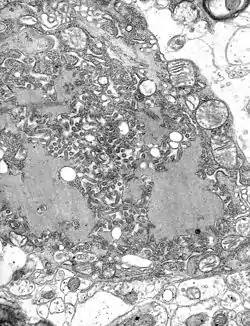

| Colorized transmission electron micrograph showing the rabies virus (in red) infecting cultured cells | |